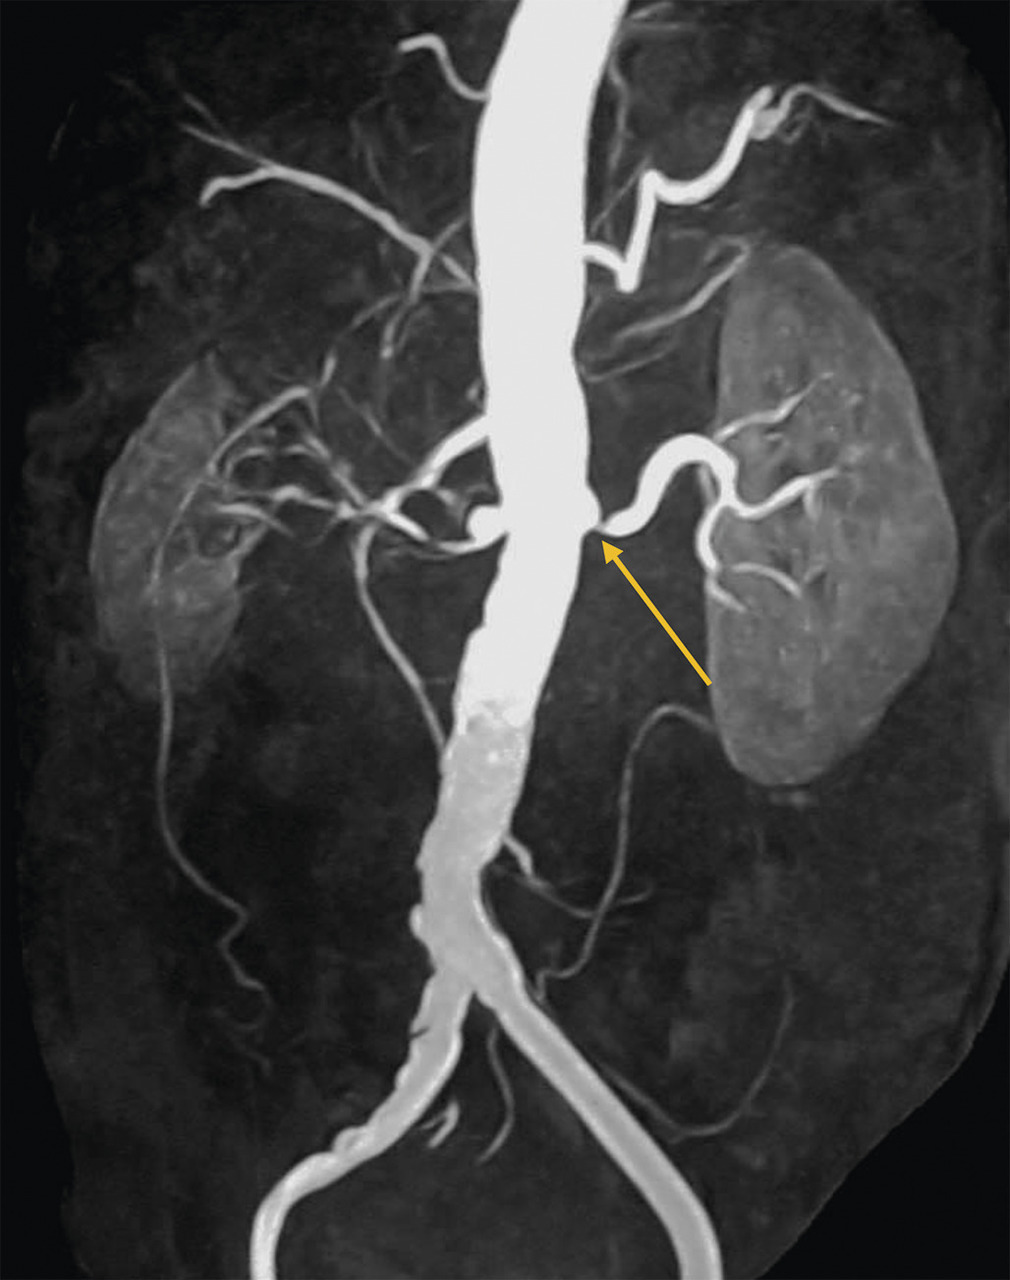

L’échographie-Doppler, l’angio-tomodensitométrie (angio-TDM [fig. 2] et l’angio-imagerie par résonance magnétique (angio-IRM) [fig. 3] permettent le diagnostic de sténose de l'artère rénale. Ils estiment à la fois le degré de sténose (exprimé en pourcentage de réduction du diamètre) et l’impact sur la vascularisation d’aval. Ces 3 examens sont validés et recommandés en première intention. Leur utilisation dépend de l’accessibilité et des habitudes locales. Il est à noter que l’écho-Doppler, très sensible et spécifique dans la sténose de l'artère rénale athéromateuse sous réserve d’un opérateur entraîné, est de sensibilité imparfaite dans la fibrodysplasie, dans laquelle l’angio-TDM est l’examen de référence.

Le tableau résume les avantages et inconvénients respectifs des 3 examens de référence. L’artériographie est réservée aux revascularisations (fig. 4), et n’a pas de place à titre diagnostique.

Dans la sténose de l'artère rénale athéromateuse, on retrouve une plaque habituellement unique, plus une moins calcifiée, ostiale, proximale ou tronculaire, responsable d’une réduction du diamètre endoluminal d’une ou des artères rénales (fig. 2 et 3).

En cas de fibrodysplasie, les lésions sont multiples, distales, souvent bilatérales, avec aspect en « collier de perles » (fig. 4). Il est recommandé, dans cette pathologie qui est souvent multifocale, de rechercher d’autres lésions artérielles (sténoses ou anévrismes) au niveau des artères digestives, cervicales et intracrâniennes.